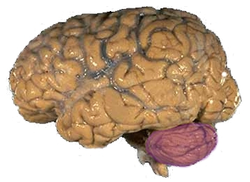

Anatomically, the human cerebellum has the appearance of a separate structure attached to the bottom of the brain, tucked underneath the cerebral hemispheres. Its cortical surface is covered with finely spaced parallel grooves, in striking contrast to the broad irregular convolutions of the cerebral cortex. These parallel grooves conceal the fact that the cerebellar cortex is actually a continuous thin layer of tissue tightly folded in the style of an accordion. Within this thin layer are several types of neurons with a highly regular arrangement, the most important being Purkinje cells and granule cells. This complex neural organization gives rise to a massive signal-processing capability, but almost all of the output from the cerebellar cortex passes through a set of small deep nuclei lying in the white matter interior of the cerebellum.[5]